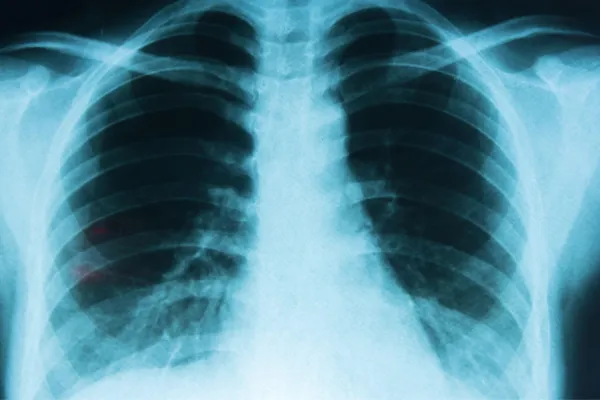

Cáncer de pulmón: cuál es el fármaco autorizado por la Anmat que previene las recaídas

Luego de la cirugía, en más del 50% de los pacientes la enfermedad vuelve a aparecer. ¿Cómo se aplica esta nueva inmunoterapia?